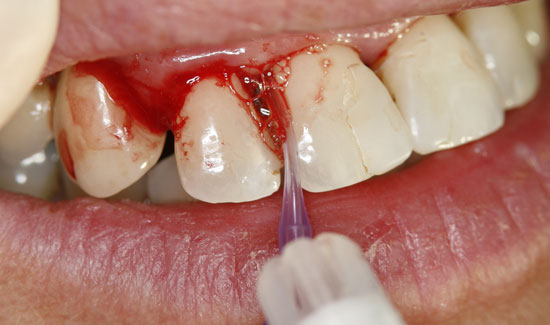

Фиг. 2: Клиничен аспект на зоната 1-2, образуване на мехурчета по възпалената тъкан. Непрекъснато всмукване в близост до зоната на употреба.